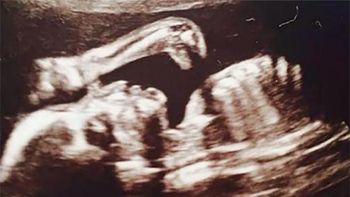

Un bebé nació este jueves con dos cabezas y un tórax y murió pocas horas después en el Hospital Zonal Monseñor Jorge Gottau, en la ciudad santiagueña de Añatuya.

Pese a los esfuerzos de los médicos, el niño, dado a luz por una joven de 22 años, falleció poco antes del mediodía, informaron fuentes del hospital.

La joven es oriunda de la localidad de Real Sayana, a unos 60 kilómetros de la ciudad donde se produjo el alumbramiento del niño, que según la descripción de las mismas fuentes tenía dos cráneos y dos troncos, aunque poseía un solo tórax.